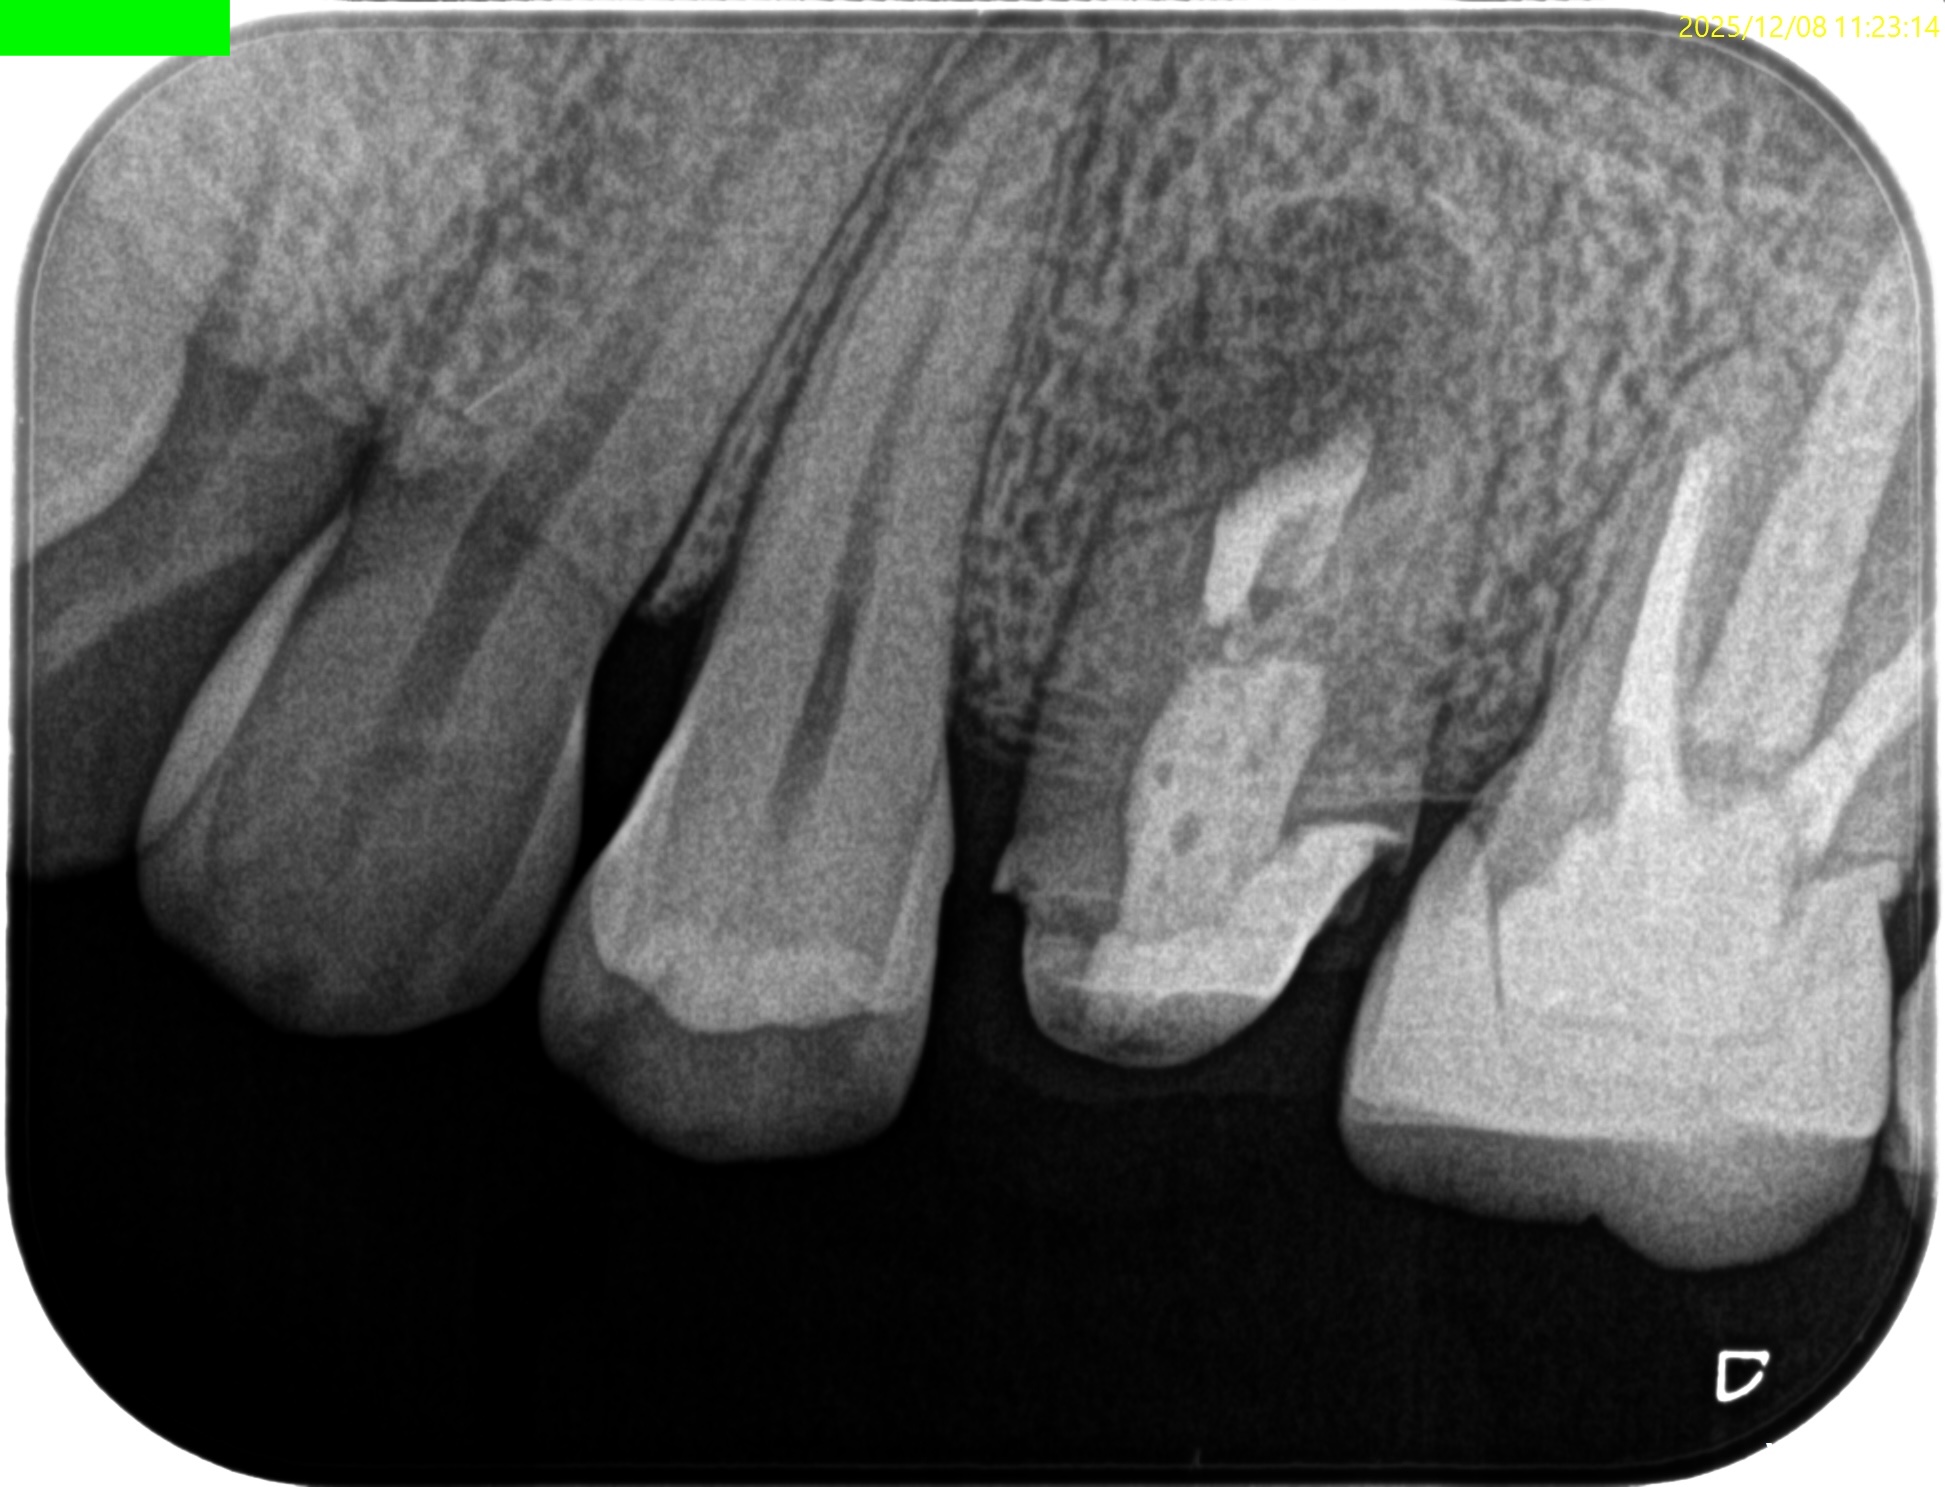

初診時と比較した。

劇的に歯槽骨が回復している。